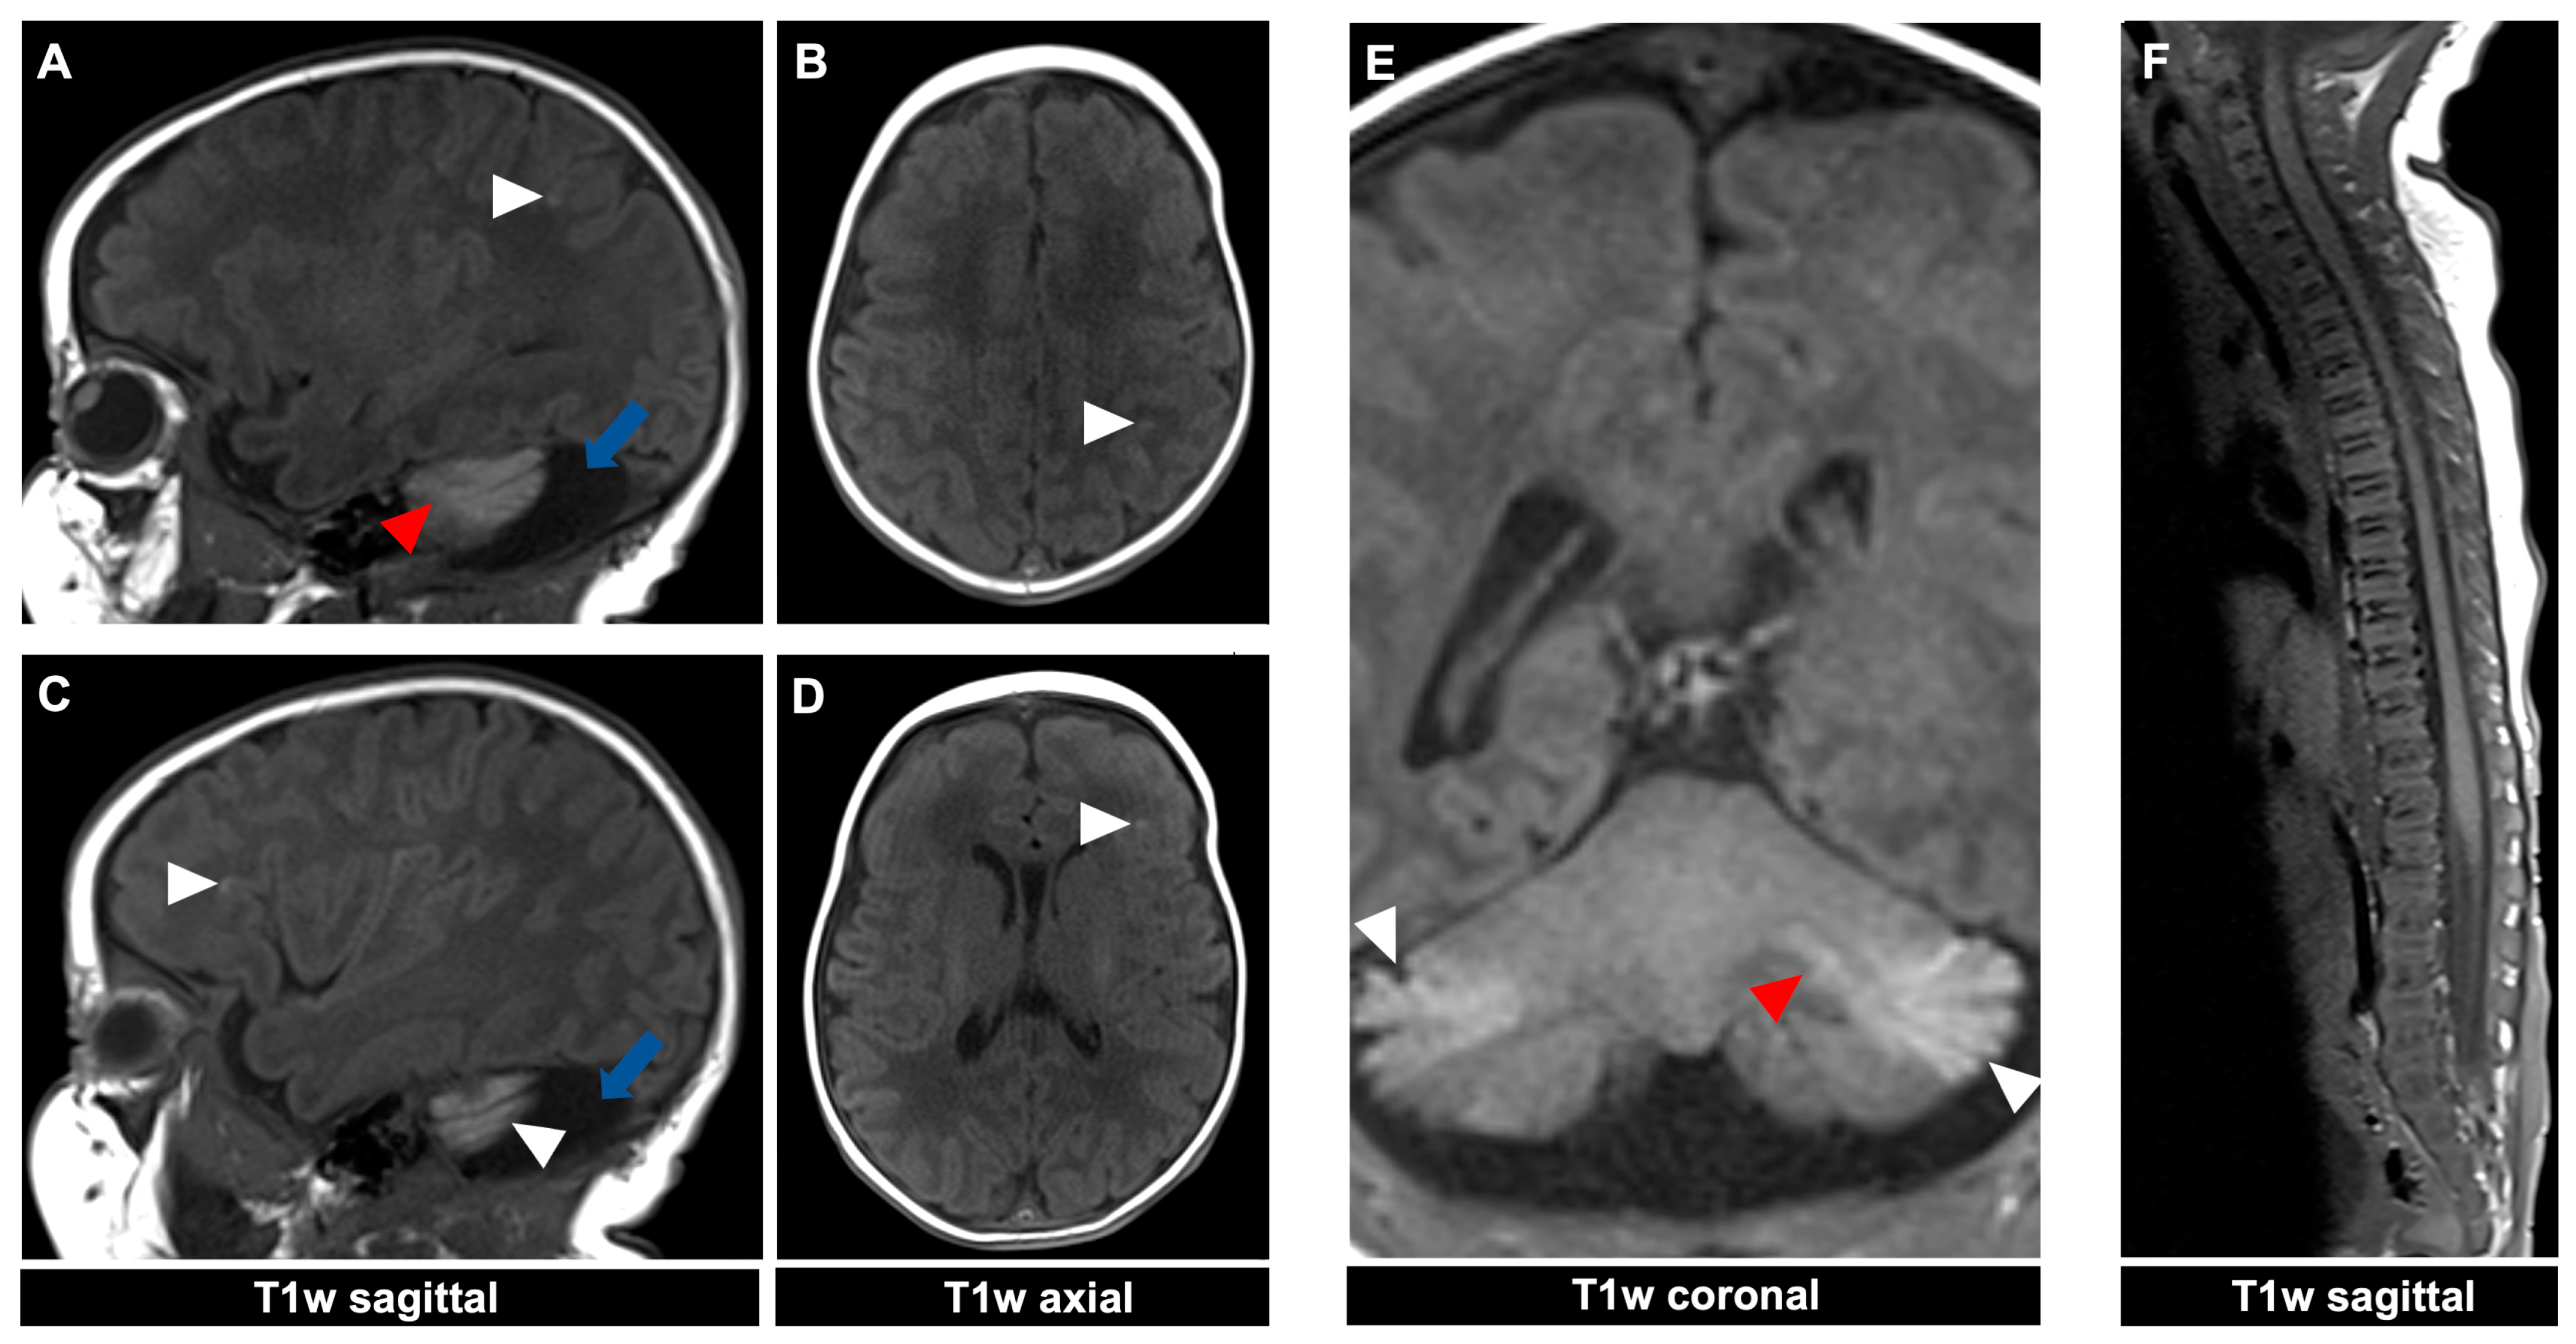

Figure 4.

MR imaging of a 23-day-old female patient with neurocutaneous melanosis (NCM) using an MRI-compatible incubator. (A–E) Intraparenchymal (red arrowhead) and leptomeningeal (white arrowhead) melanosis imaging findings demonstrate a high T1 signal. The acquired sagittal and corresponding axial image examples (A–D) illustrate that acquiring two different planes of T1-weighted sequences is advantageous, as it is sometimes difficult to distinguish between leptomeningeal and intraparenchymal manifestations. The patient also has an infratentorial arachnoid cyst ((A,C) blue arrow). (F) Spinal MRI showed no abnormalities. T1w = T1-weighted.